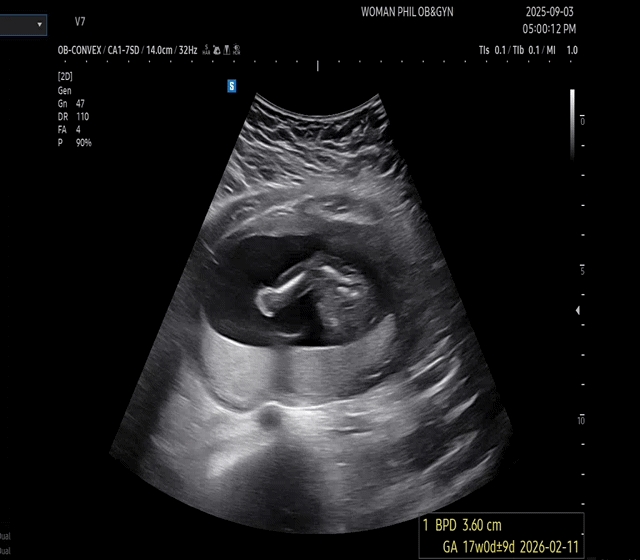

안녕하세요 맘님들! 우리 아가의 성별을 여쭙고 싶어요! 의사쌤께서 100프로 확답 주신게 아니다보니 너무 궁금한 마음, 신랑이 딸을 너무 원해서 혹시나 기대하는 마음에 선배맘님들 조언을 구해보아요! 저는 넘나 아들같은데 다들 어떻게 보이시나용?